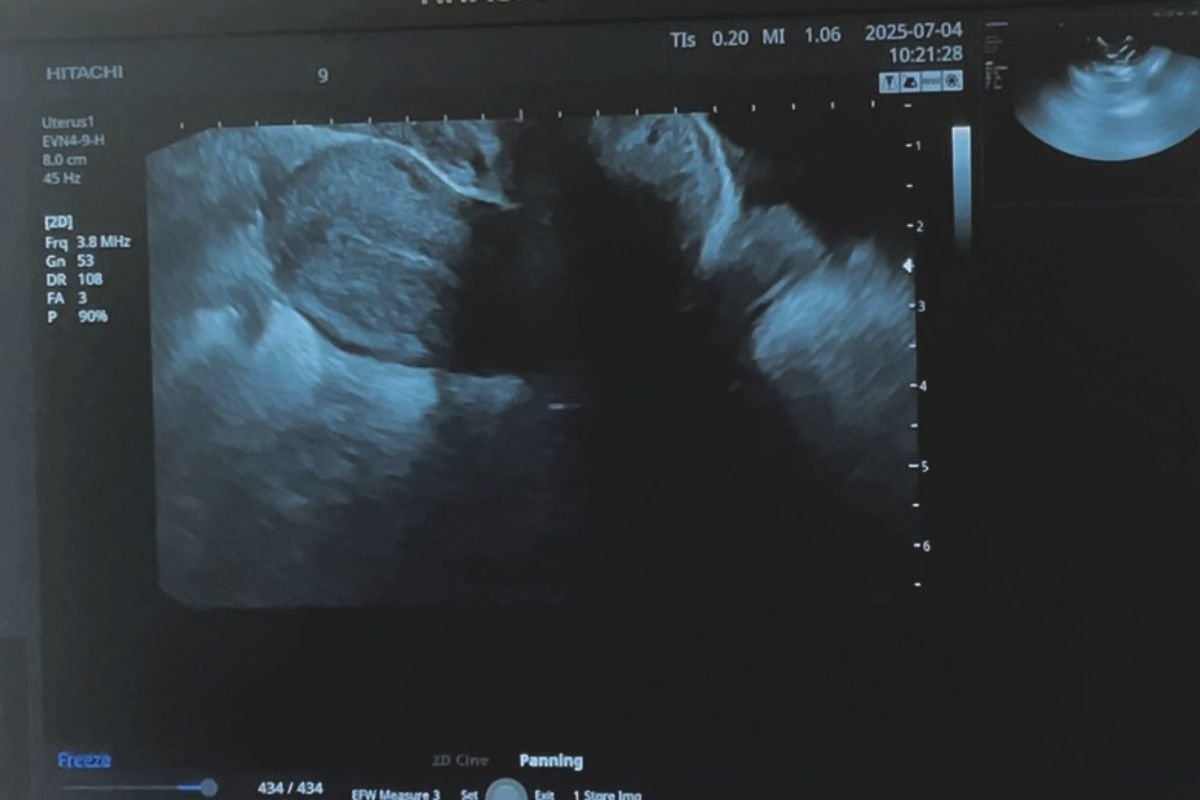

オプションで受けました!エコー検査

子宮と卵巣の状態を知るためまずはエコー!

子宮内膜や卵巣の中、小さな腫れはエコーでないとわかりません。病気のサインかもしれない自覚症状は、問診で必ず伝えましょう! プロープ挿入感は頸がん検査のクスコとほぼ同じ。子宮頸がん検診はできれば毎年、エコーもついでに受けるといいそう。なんと鈴木はエコーで多のう胞性卵巣所見と発覚! 卵胞が排卵できず卵巣内にたまり、周期が不安定になるので、妊娠しにくいことも。